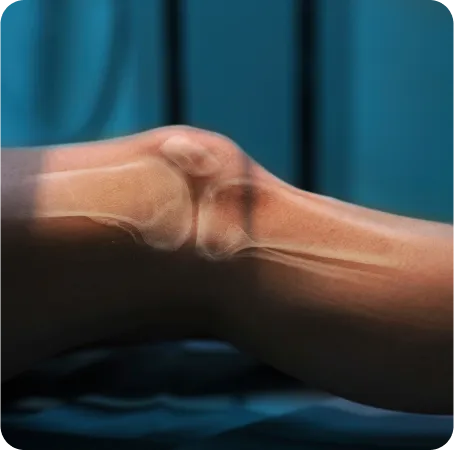

• KHF(Knee&Hip Flex posture)타입 : 슬관절굴곡 - 고관절굴곡 자세

스포츠 재활 도수치료

스포츠 재활 전문 물리치료사의 정확한

근력 측정과 기능적 움직임 평가를 통해

통증을 치료하고 근력과 관절 가동범위를 회복하여

치료의 만족도를 높입니다.

수술 후 재활 도수치료

의사와 물리치료사의 충분한 논의 후

수술 봉합 부위 유착으로 인한 관절가동범위

제한을 풀어주고 통증이 발생하지 않도록

재활을 진행합니다.